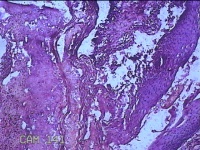

宫颈组织

性别

女

年龄

44岁

临床诊断

宫颈赘生物

一般病史

发现宫颈赘生物2年余。

标本名称

大体所见

灰白暗红色组织3.8x1.5x0.8cm一块,表面光滑,以宫颈12点缝线标记处切开,切面灰白粉红色,质软,宫颈3点处见灰白粉红色囊性肿物1.8x1.5x0.3cm一个,切开肿物,内见大量乳白色内容物,囊壁厚0.1cm。